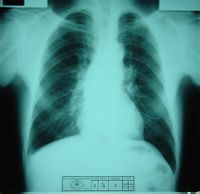

2. 胸部X線表現:主要表現為廣泛的慢性纖維組織增生,其中包括肺泡與支氣管周圍以及淋巴結中的纖維結締組織增生。X線胸片上除表現不規則小陰影,肺門增大外亦可見到明顯的胸膜增厚,個別病例可表現為同兩肺廣泛的粗細網影,並有細小而密度不高的顆粒狀陰影。